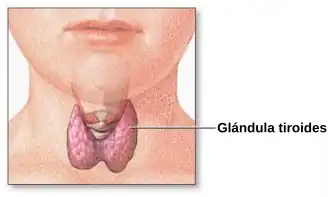

Sistema endocrino

El sistema endocrino es el conjunto de órganos y tejidos del organismo que segregan un tipo de sustancias llamadas hormonas. Las hormonas son mensajeros químicos liberados por células, que alcanzan el torrente sanguíneo para regular a distancia diferentes funciones corporales, entre ellas la velocidad de crecimiento, la actividad de los tejidos, el metabolismo y el desarrollo y funcionamiento de los órganos sexuales. Una vez alcanzado el punto de destino, estos mediadores se unen a su receptor específico ubicado en la célula diana.[32] Las glándulas principales productoras de hormonas son la glándula tiroides que produce tiroxina, el páncreas que produce insulina, la hipófisis que secreta numerosas hormonas y las glándula suprarrenal que producen cortisol, aldosterona y adrenalina.